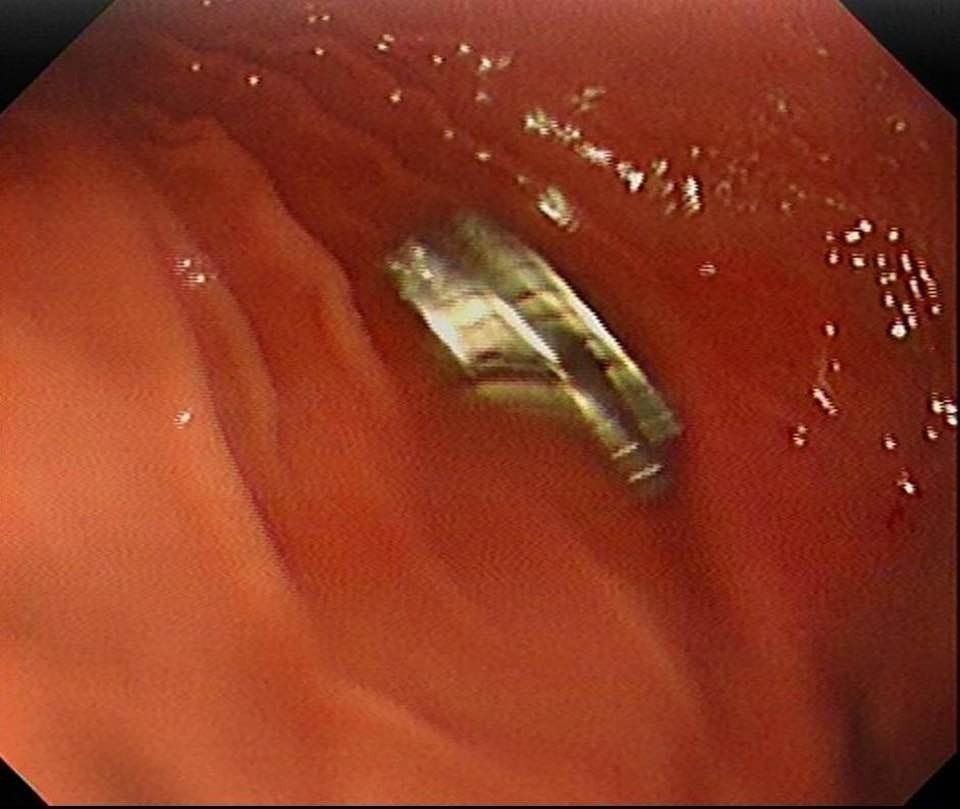

Edinilen bilgiye göre, Erzurum’da bir çocuk evde bulunan 19 tane mıknatısı yuttu. Çocuğun rahatsızlanması sonucu durumu öğrenen aile hastaneye başvurdu. Daha sonra çocuk Elazığ’a sevk edildi. Fırat Üniversitesi Çocuk Gastroenteroloji Hepatoloji ve Beslenme Bilim Dalı Başkanı Prof. Dr. Yaşar Doğan, çocuk hastanın yemek borusuna yapışmış 19 mıknatısı endoskopik yöntemle çıkardı.

Mıknatıslar uzun süre yemek borusunda takılı kaldığı için yemek borusu ve mide girişinde zedelenmeler olurken, çocuğun sağlık durumunun iyi olduğu ve taburcu edildiği öğrenildi.